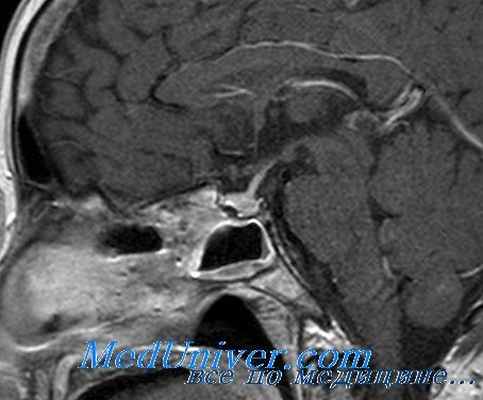

Обнаруженные гормональные изменения, свидетельствующие о наличии смешанной опухоли гипофиза, явились весомым основанием для динамической ревизии его морфологического состояния с помощью компьютерной и магнитнорезонансной томографии. При компьютерной томографии в гипофизарной ямке визуализируется объемное образование (округлой формы, диаметром 11 мм, повышенной до 40 ед. Н плотности), интенсивно накапливающее контрастное вещество; параселлярная цистерна расширена. При магнитно-резонансной томографии наличие эндоселлярной аденомы гипофиза подтверждено.

Заключительный диагноз: интраселлярная соматотропин- пролактинпродуцирующая аденома гипофиза, хроническая внутричерепная гипертензия у девочки 9 лет с клиникой ги- гантизма-акромегалии-раппеro пубертата. Назначено комбинированное медикаментозное (парлоделом) и лучевое (прото- нотерапия) лечение.